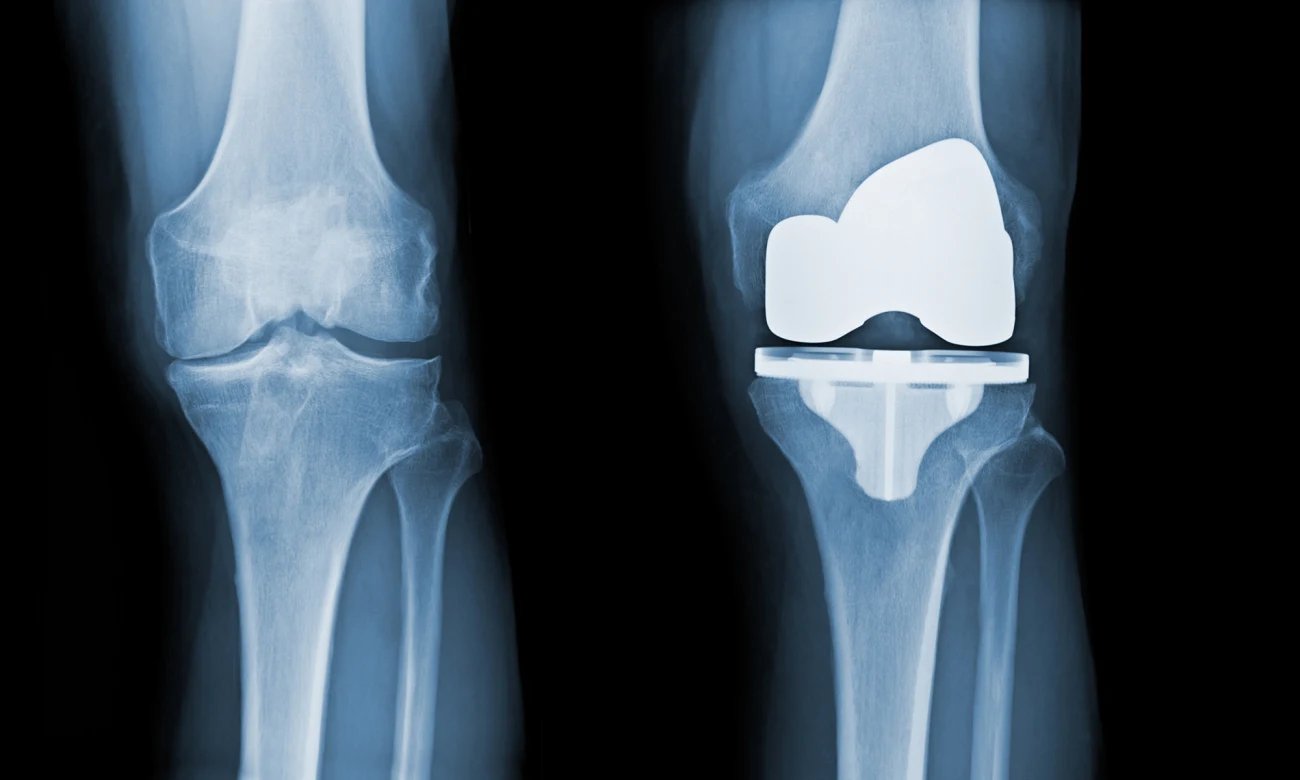

Common joint replacement surgeries include

• 1. TOTAL HIP REPLACEMENT

• 2. TOTAL KNEE REPLACEMENT

• 3. TOTAL SHOULDER REPLACEMENT

• 4. REVERSE SHOULDER REPLACEMENT

• 5. TOTAL ELBOW REPLACEMENT

• 6. TOTAL ANKLE REPLACEMENT

Why Joint Replacement At Summit Orthopaedic Hospital?

• 1. MINIMAL INCISION

• 2. MINIMAL SOFT TISSUE DAMAGE

• 3. MINIMAL BLOOD LOSS AND NEED FOR BLOOD TRANSFUSION

• 4. MINIMAL HOSPITAL STAY

• 5. MINIMAL POSTOPERATIVE PHYSIOTHERAPY AND REHABILITATION

• 6. MINIMAL COST